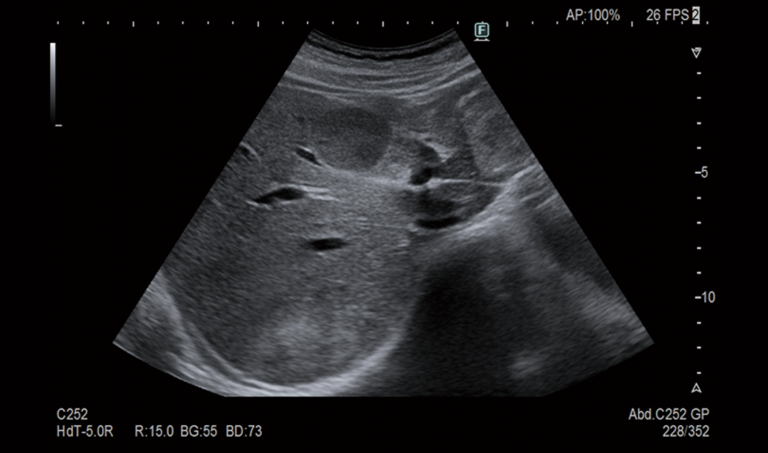

Chúng tôi xin giới thiệu một trong những thiết bị tiên tiến đang được sử dụng tại phòng khám. Chính là máy siêu âm FUJIFILM ARIETTA650 DeepInsight SE.

Như Quý vị đã biết, siêu âm là phương pháp dùng sóng âm để ghi lại hình ảnh bên trong cơ thể. Và chiếc máy siêu âm này, tuy nằm trong thân máy nhỏ gọn nhưng lại được tích hợp công nghệ siêu âm tối tân của Nhật Bản.

Xin mời Quý vị xem qua hình ảnh siêu âm bên dưới:

Ngay cả khi không quen với hình ảnh siêu âm, cũng không khó để có thể nhận thấy độ sắc nét và chi tiết vượt trội.

Thiết bị này có khả năng hiển thị rõ những bất thường mà các dòng máy cũ không thể phát hiện. Độ rõ nét đến mức như thể chúng ta đang nhìn trực tiếp vào bên trong cơ thể chứ không phải là thông qua máy móc.

Thao tác siêu âm được thực hiện trên bề mặt da, không đau, không gây khó chịu, hay bất cứ áp lực nào lên cơ thể. Dù vậy, thiết bị này vẫn có thể phát hiện tế bào ung thư gan, khối u bên trong cơ thể, sỏi mật, polyp, những bất thường ở dạ dày, tụy, tử cung… và nhiều thay đổi nhỏ khác.

Và điều quan trọng hơn chính là tại đây, những hình ảnh siêu âm này được đọc và phân tích bởi các kỹ thuật viên và bác sĩ Nhật Bản giàu kinh nghiệm, nổi tiếng không bỏ sót bất kỳ chi tiết nào.